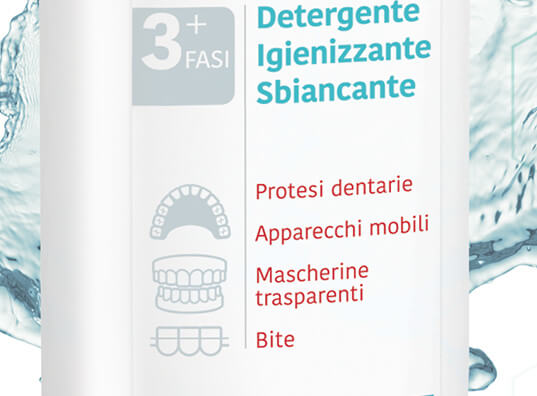

Per il lancio di questo nuovo prodotto, una vera novità per il mondo dell’ortodonzia, dovevamo creare un visual che facesse capire che i tradizionali prodotti per la pulizia delle protesi, delle invisalign etc. si era evoluta verso una soluzione unica, dedicata al consumatore e approvata dal dentista.